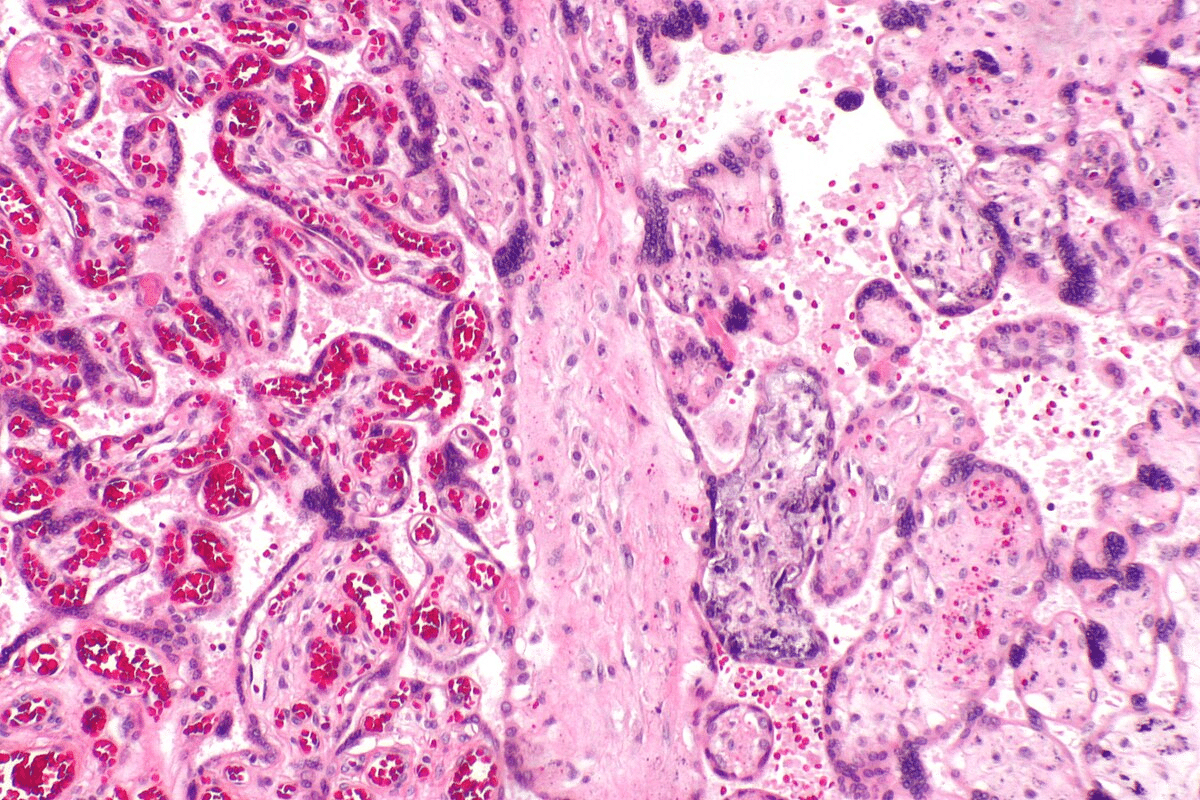

Skin Biopsy Findings

A skin biopsy is often needed to confirm SCLE Lupus. The biopsy shows changes in the skin that are typical of SCLE. These changes, along with other signs, help doctors make a diagnosis.